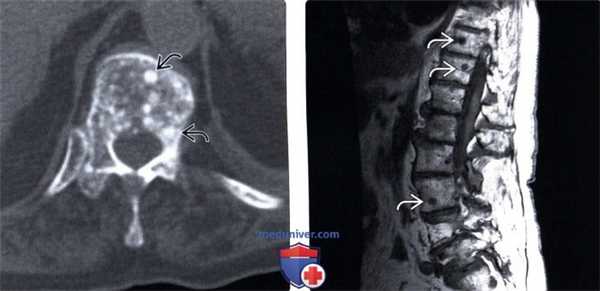

(Слева) Аксиальный КТ- срез: множественные округлые узелки склероза в теле нижнегрудного позвонка, представляющие собой бластические метастазы рака молочной железы.

(Справа) На Т1-ВИ у этой же пациентки определяются бластические метастатические поражения, имеющие форму округлых узелков очень низкой интенсивности в телах грудных и поясничных позвонков.